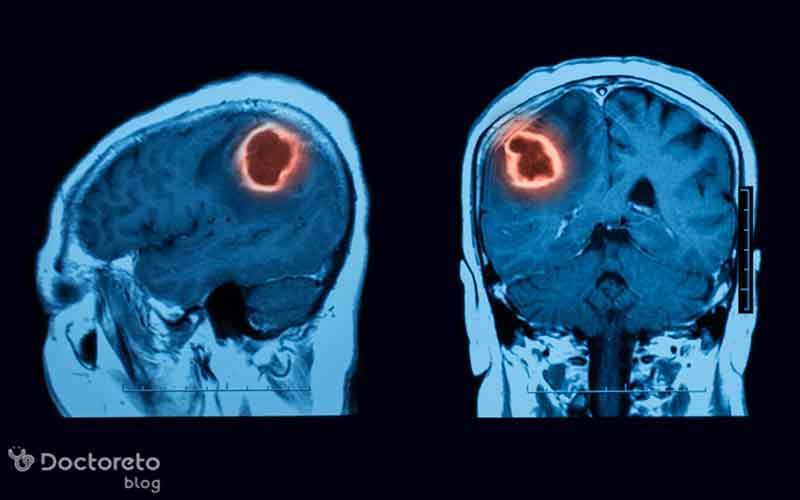

علائم تومور مغزی در جوانان میتوانند متنوع و گاهی غیرمشخص باشند. زیرا بخش اصلی مغز، یعنی مخ، عملکردهای مختلفی مانند حرکت، حافظه، رفتار و احساسات را کنترل میکند. تومورهای مغزی که در قسمتهای مختلف مخ رشد میکنند، ممکن است نشانههای متفاوتی ایجاد کنند. در جوانان، شایعترین علائم شامل سردرد و حالت تهوع یا استفراغ است که به ویژه صبحها و همراه با تغییرات فشار مغزی بروز میکنند. علاوه بر علائم جسمانی، تغییرات رفتاری و روانی نیز در بعضی جوانان مبتلا به تومور مغزی مشاهده میشود؛ برای مثال فرد ممکن است در مدرسه گوشهگیر و بدخلق شود و در انجام وظایف روزانه با مشکل مواجه شود برای بررسی دقیق تر به دکتر مغز و اعصاب مراجعه کنید. در این مقاله از دکترتو به بررسی دقیقتر این علائم خواهیم پرداخت. با ما همراه باشید.

تومور مغزی در جوانان میتواند طیف وسیعی از علائم جسمی و رفتاری ایجاد کند که به محل و اندازه تومور بستگی دارد. علائم تومور مغزی ممکن است به تدریج یا ناگهانی ظاهر شوند. نشانه های تومور مغزی در جوانان بسته به محل تومور شدت و نوع آنها متفاوت است، بنابراین تشخیص زودهنگام به پیشگیری از عوارض بلندمدت کمک زیادی میکند. برخی از شایعترین علایم تومور مغزی در جوانان عبارتند از:

زنان جوان ممکن است علائم را زودتر گزارش کنند، که به تشخیص سریعتر کمک میکند. همچنین در تومورهای پینهآل، اختلالات خواب یا هورمونی (مانند تأخیر بلوغ) شایعتر است. بهتر است به نکته توجه کنید که علائم در هر دو جنس غیراختصاصی هستند و میتوانند با میگرن، استرس یا عفونت اشتباه گرفته شوند. تشخیص با MRI یا CT اسکن تأیید میشود.

علائم تومور مغزی در جوانان میتوانند متنوع و گاهی مبهم باشند. این علائم شامل سردرد، تهوع، تغییرات رفتاری، مشکلات بینایی یا شنوایی، تشنج و اختلال تعادل هستند. شناخت این نشانهها و توجه به هر تغییر ناگهانی یا غیرعادی در بدن و رفتار جوانان اهمیت زیادی دارد؛ زیرا تشخیص زودهنگام شانس درمان موفق و بهبود کیفیت زندگی را افزایش میدهد. اگر هر یک از علائم هشداردهنده مشاهده شد، مراجعه سریع به پزشک متخصص مغز و اعصاب و انجام آزمایشهای تصویربرداری و ارزیابیهای لازم ضروری است.